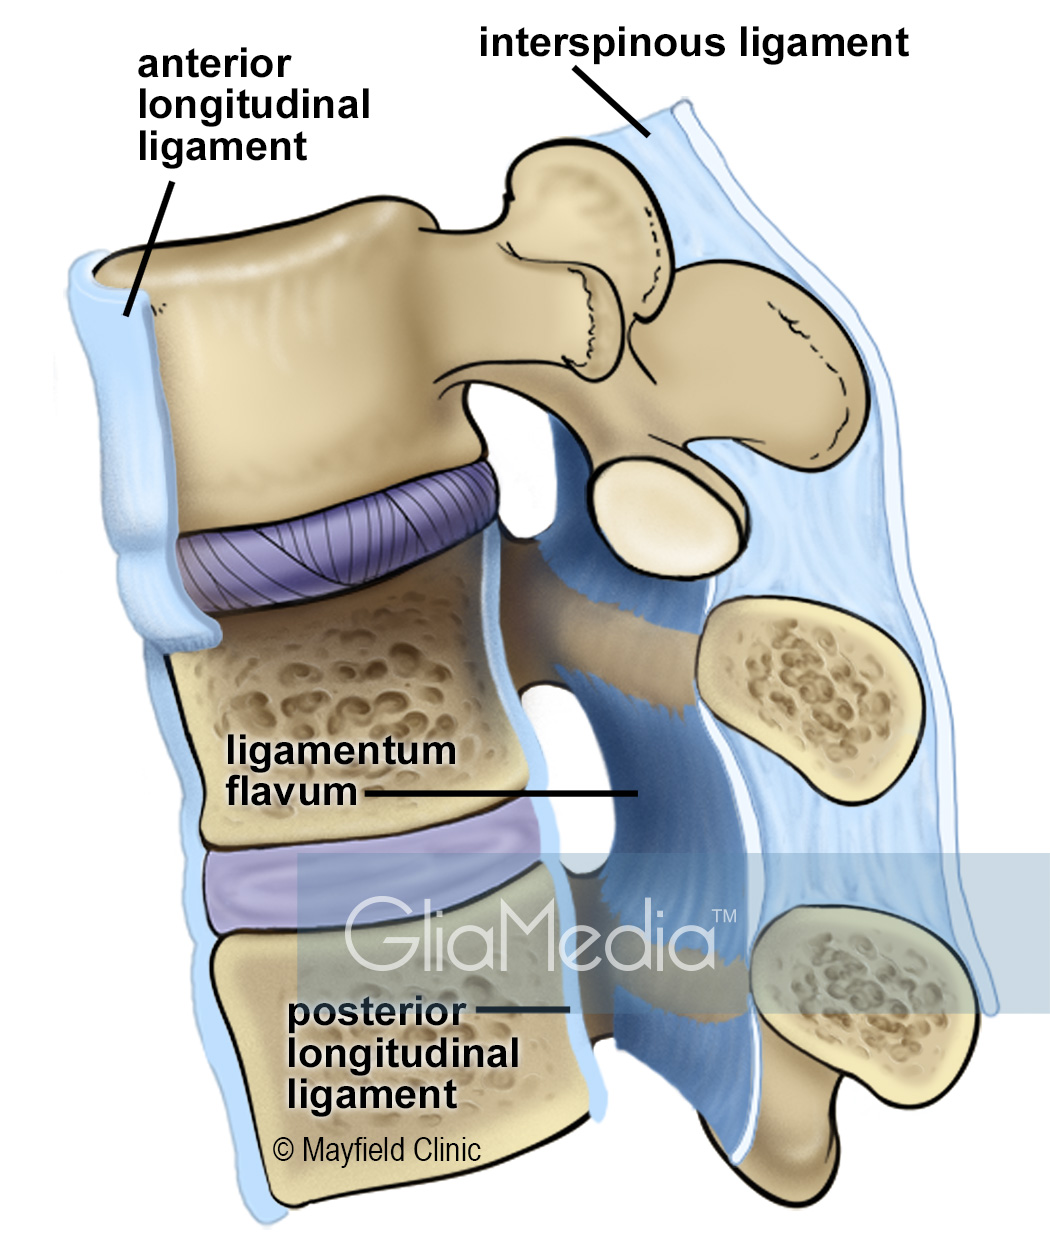

Pure Health - Anatomy 101 - Supraspinous ligament and interspinous ligament 📚 The supraspinous ligament and interspinous ligament work together to limit flexion of the spine by limiting separation of the spinous

DOCS - The interspinous ligament is located between the spinous processes of adjacent vertebrae in the spine. It extends from the base of one spinous process to the apex of the next,